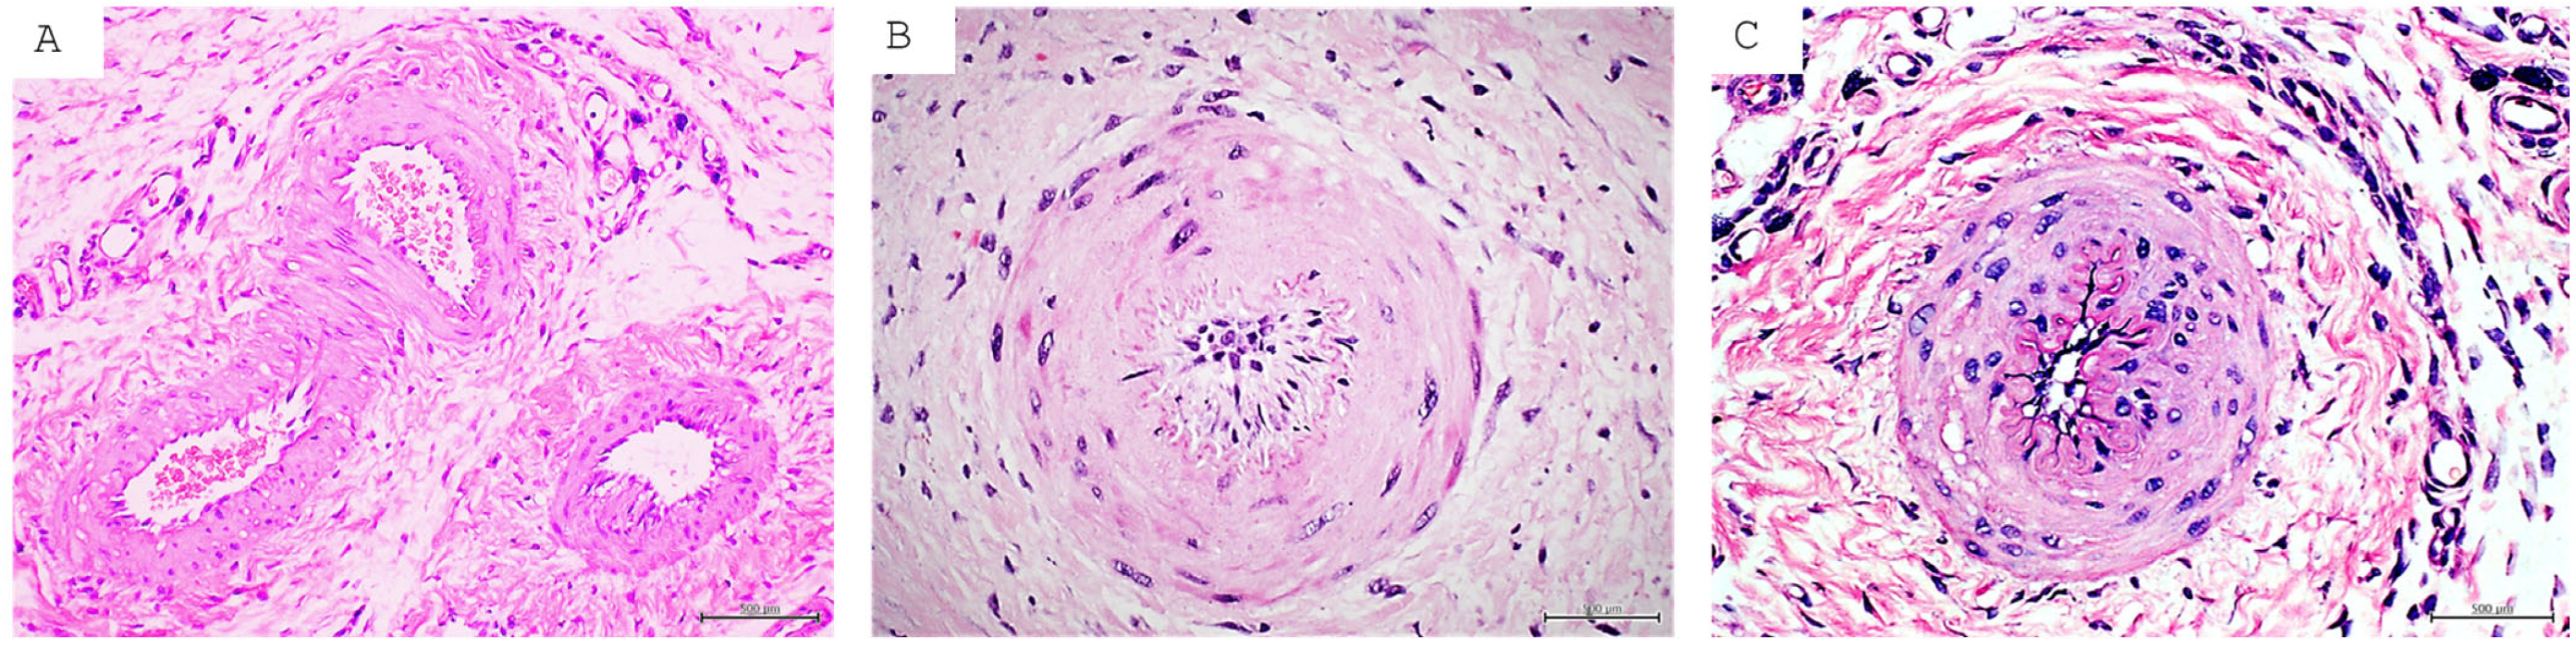

| DFU | Consequent to long-term hyperglycemia and cytotoxic by-products like AGEs and ROS. Ulcer onset by external factors like trauma, funguses, etc. Major cause of amputation and disability. Two main clinical classifications: ischemic and neuropathic. GT histopathology with large differences between the two clinical forms. The former with poor and abnormal angiogenesis, the latter with extensive nerve fiber edema and axonal degenerative changes. | About 40% of patients will experience recurrence within the first year of re-epithelialization. The wound is preferentially considered in “remission” instead of healed [31]. | Exhibits the broadest and deepest characterization of epigenetic abnormal codes, introduced by hyperglycemia, ROS, and AGEs. This epigenetic code is the foundation of metabolic memory which sustains the perpetuation of complications, including the poor healing response in skin and mucosa. The epigenetic anomalies supporting inflammation, senescence, and oxidative stress have been identified. They include changes in DNA methylation pattern, histone modifications, and non-coding RNA [97,98]. |

| PI | Largely prevailing wound in both elder and non-elder subjects mostly with spinal cord injury. Although with endogenous and external predisposing factors, the triggering one is prolonged pressure, friction, or shearing force over a bone prominence. It is a cause of multimorbidity and mortality in elder populations. At the histopathological level, the main pressure targets are large dermal vessels, leading to muscle necrosis and a cascade of damage concluding in full-thickness skin necrosis and adjacent vessel thrombosis. | The incidence of recurrence may span 5.4–73.6%. The most commonly reported site of recurrence is the ischium [74]. | Epigenetic studies on PI are scarce. To our understanding a major and recent contribution is the identification of genes related to recurrence. Upregulated activity in genes involved in metabolic pathways (ENOSF1) and pathways in biological senescence (TMEM158) and downregulated activity in the interleukin 17 signaling pathway are directly involved in antimicrobial protection in vivo. Conversely, persons without recurrent PIs have upregulated activity in genes related to bioprocesses such as regulators of vasodilation (TAC3) and downregulated activity in biological pathways related to addiction (FOS, JUN, FOSB) [99]. |

| VLU | Largely prevailing chronic wound consequent to long-term chronic venous disease. It imposes a poor quality of life. VLUs exhibit a complex and intricate pathophysiological mechanism, involving hemodynamic, cellular, and molecular alterations of macro- and microcirculation, which ultimately drives skin necrosis by venous ischemia, hypertension, and hypoxia. Histological examination reveals dilated veins, hemosiderin and fibrin deposition, sclerosis hemorrhage, and vascular fibrin cuffs. Acute phase lipodermatosclerosis shows lymphocytic and inflammatory cell infiltrate. | VLUs are characterized by repeated cycles of healing and recurrence in 60% to 70% of patients [28,94]. The median recurrence time is 42 weeks with a recurrence incidence of 22% within three months after re-epithelialization, 39% at the sixth month, and 57% by the twelfth month [95]. | Numerous upregulated miRNAs have been shown to participate in prolonging VLU inflammation and limiting angiogenesis. Concurrently, the involvement of upregulated miRNA inhibited keratinocyte proliferation, prolonged inflammation, and impaired the healing response [100]. |